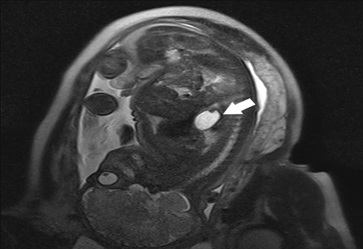

Male newborn, born to a G4P4 mother in her 40s, without previous history of miscarriages, familial malformation syndromes or parental consanguinity. Pregnancy was uncomplicated. However, an ultrasound at 32 weeks gestation revealed an anechogenic formation posterior to the fetus’ heart, suggestive of an intrathoracic stomach, without pulmonary hypoplasia. Magnetic resonance imaging at 35 demonstrated the same structure, contiguous to the esophagus, with a tubular morphology and liquid content compatible with a hiatal hernia (figure 1). Additionally, a fetal echocardiogram at 35 weeks showed an aortic isthmus narrowing (3mm in the sagittal plane, z-score -2.4). The neonate was born at 39 weeks via spontaneous noncomplicated vaginal delivery. Because of the known gastric hernia, nasotracheal intubation was tried immediately after birth. However, the baby showed no respiratory compromise, with spontaneous breathing and normal oxygenation, so further attempts were not performed. He was in good condition at birth with Apgar scores of 9 at one minute and 10 at five and ten minutes. On examination, generalized wrinkled and redundant skin were noted, more prominently involving the face, eyes, and limbs (figure 2), giving an aged appearance. Additional findings included small palpebral fissures, palmar hyperlinearity, inverted nipples, and increased inter-nipple distance.

Figure 1: Fetal Magnetic Resonance Imaging (MRI) at 35 weeks: A structure with fluid signal is in a medial location (arrow) posterior to the heart, with a tubular morphology and contiguity with the esophagus. This structure measures 35 x 20 x 25 mm and has a thin, regular wall with folds inside, compatible with a herniated stomach.